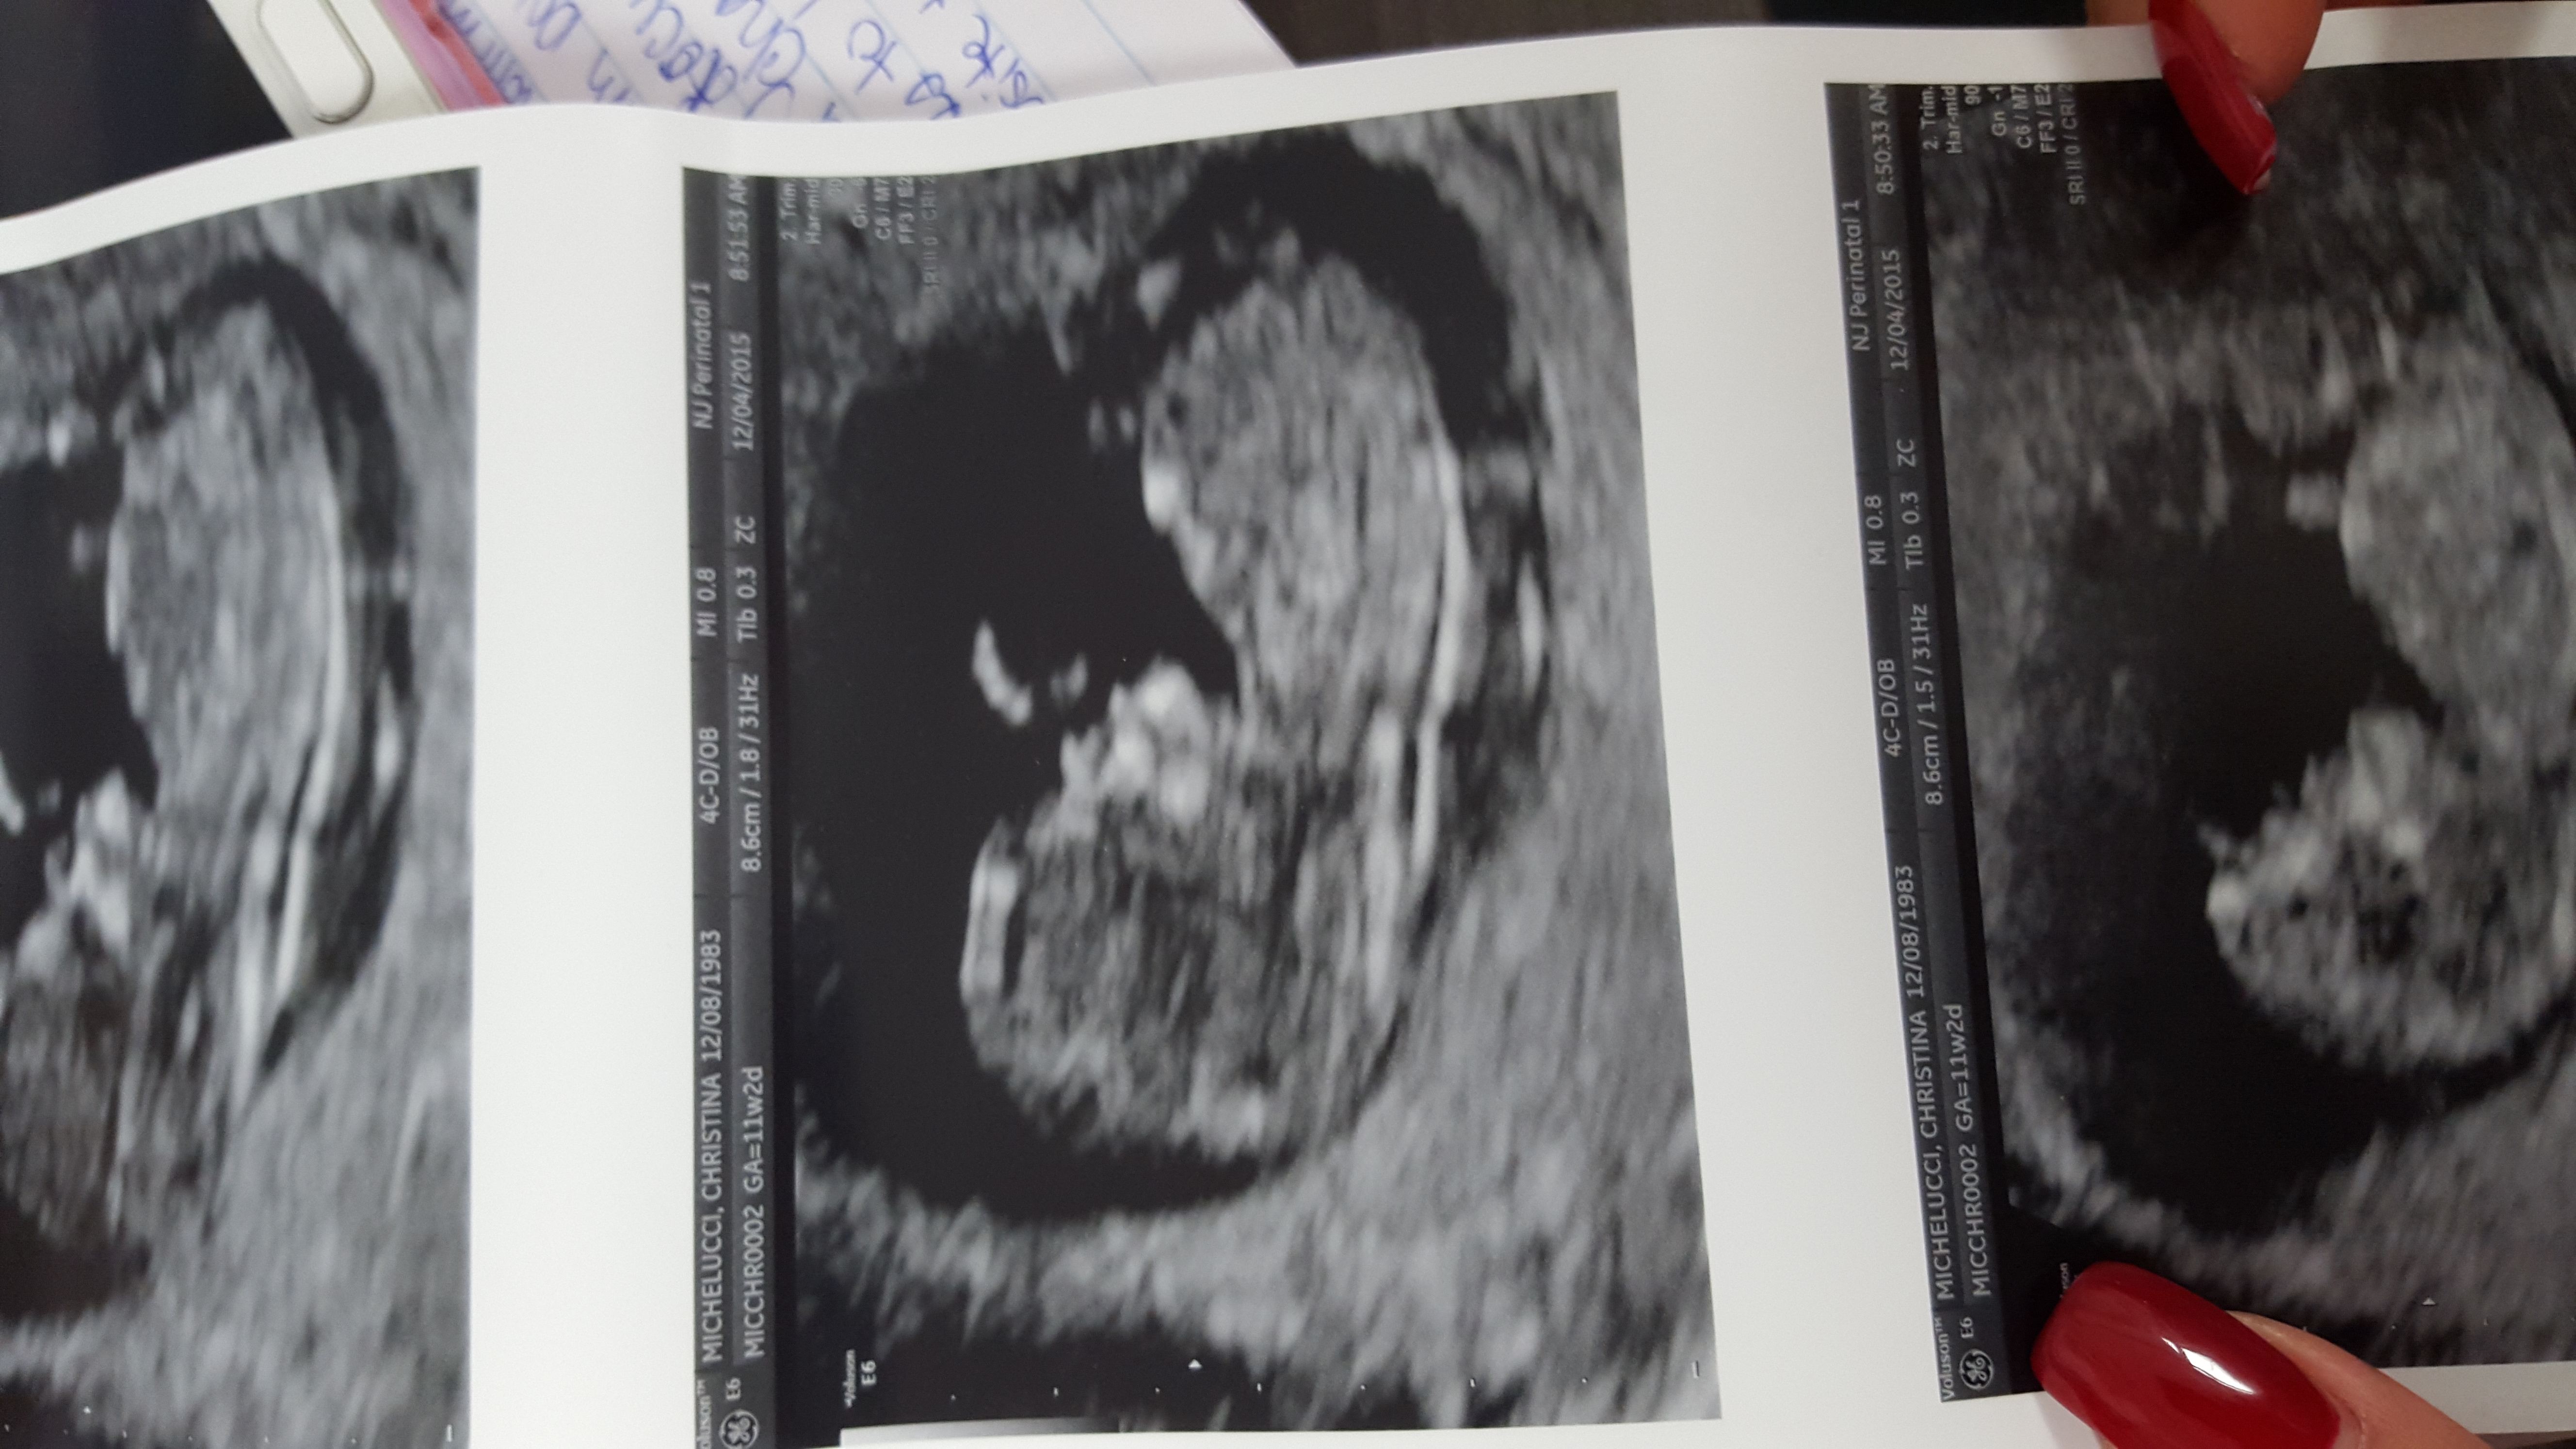

Twins!!!!!! I had two ultrasounds, one week apart.

I'm having twins too!! How far along are you?